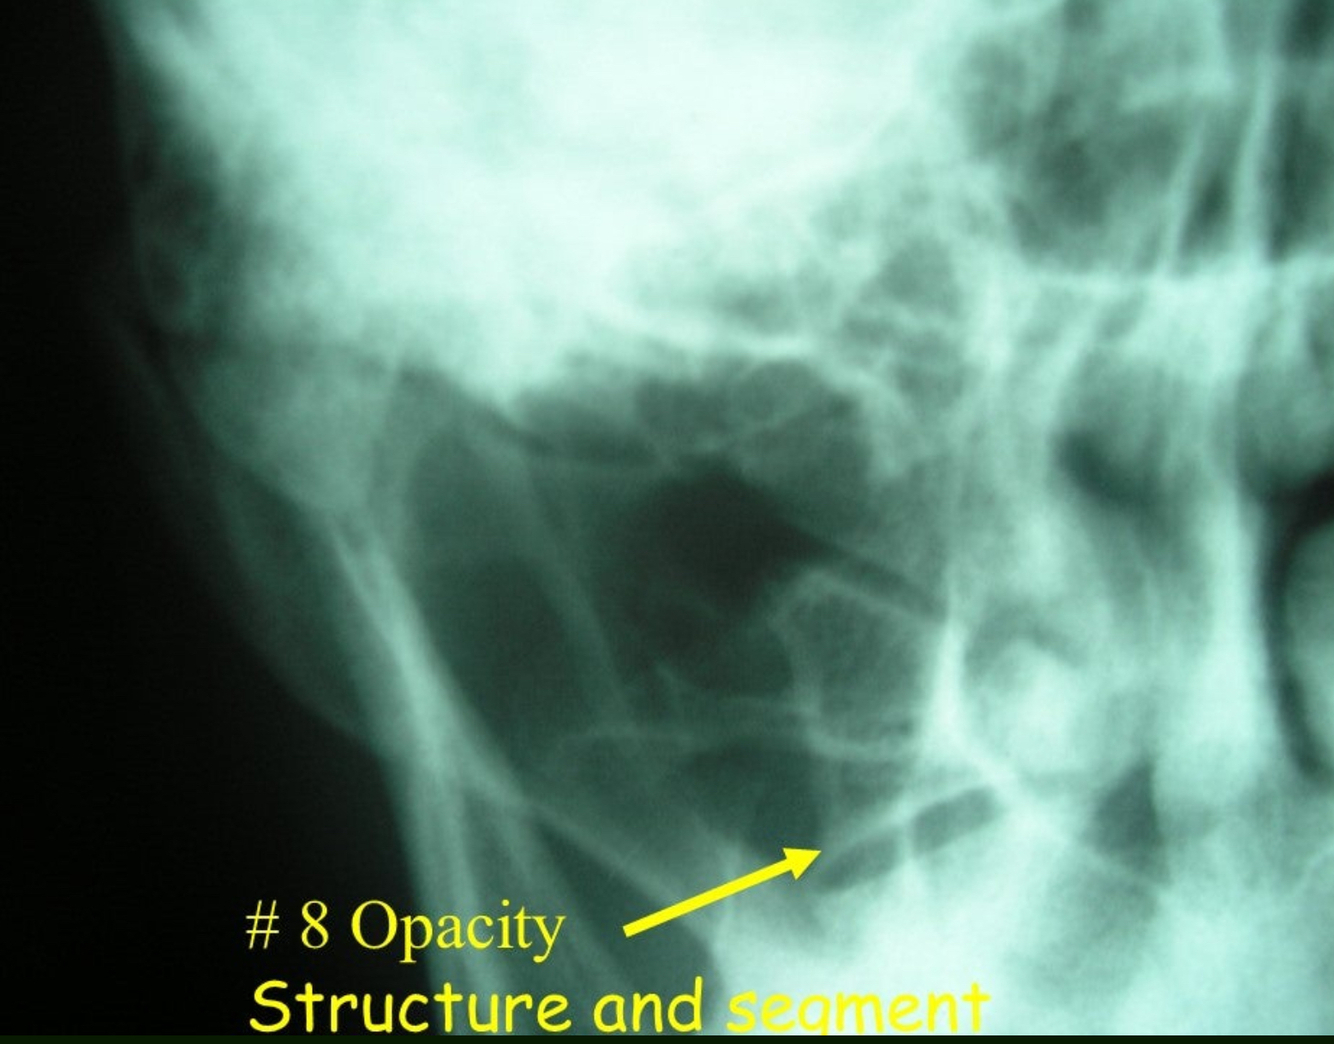

8

Q

What is 39?

A

rib 1